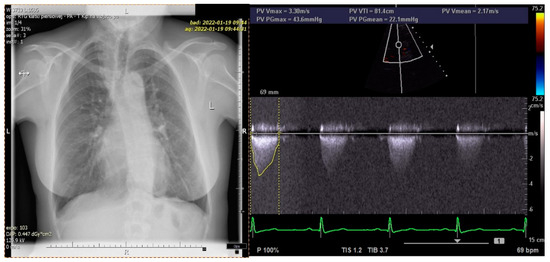

Figure 4). The patient’s chest X-ray reveled dilated bronchial vessels, and an ECHO examination showed an increased peak velocity of blood in the PA, indicating stenosis (at the level of the APW repair), which was stable and subclinical (

Figure 5). The patient had a healthy female child without any congenital anomalies.